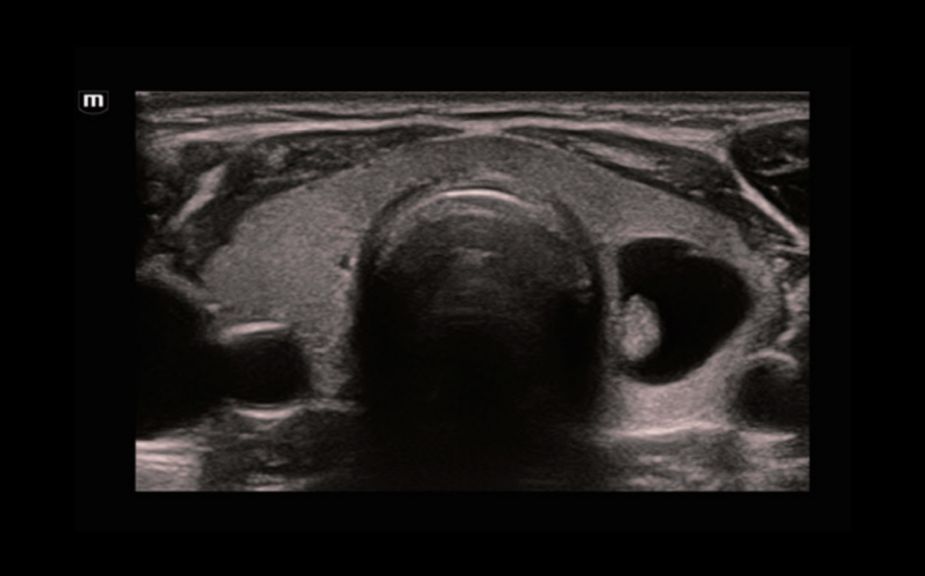

HiFR STE –Ĺ–ĺ–≤–ĺ–ĺ–Ī—Ä–į–∑–ĺ–≤–į–Ĺ–ł—Ź –ľ–ĺ–Ľ–ĺ—á–Ĺ–ĺ–Ļ –∂–Ķ–Ľ–Ķ–∑—č

HiFR STE –Ņ–Ķ—á–Ķ–Ĺ–ł